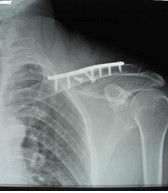

本病的輔助檢查方法主要是影像學檢查,鎖骨骨折常發生在中段。多為橫斷或斜行骨折,內側斷端因受胸鎖乳突肌的牽拉常向上後移位,外側端受上肢的重力作用向內、下移位,形成凸面向上的成角、錯位縮短畸形。1.X線檢查

疑有鎖骨骨折時需攝X線像確定診斷。一般中1/3鎖骨骨折拍攝前後位及向頭傾斜45°斜位像。拍攝範圍應包括鎖骨全長,肱骨上1/3、肩胛帶及上肺野,必要時需另拍攝胸片。前後位像可顯示鎖骨骨折的上下移位,45°斜位像可觀察骨折的前後移位。

外1/3鎖骨骨折中,一般可由前後位及向頭傾斜40°位X線像做出診斷。鎖骨外端關節面骨折,常規X線像有時難以做出診斷,常需攝斷層X線像或行CT檢查。

鎖骨內1/3前後位X線像與縱隔及椎體相重疊,不易顯示出骨折。拍攝向頭傾斜40°~45°X線像,有助於發現骨折線。在檢查時,不能滿足於X線正位片未見骨折而診斷為軟組織損傷,需仔細檢查是否有鎖骨內端或對局部骨折徵象,以便給予正確的診斷。

CT檢查多用於複雜的橈骨骨折,如波及關節面及肩峰的骨折。尤其對關節面的骨折優於X線檢查。